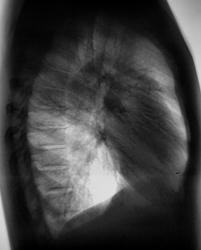

102._Rasshifrovka..jpg

А на боковой рентгенограмме, вроде-бы кропноочаговая тень не одна? А вроде-бы две?